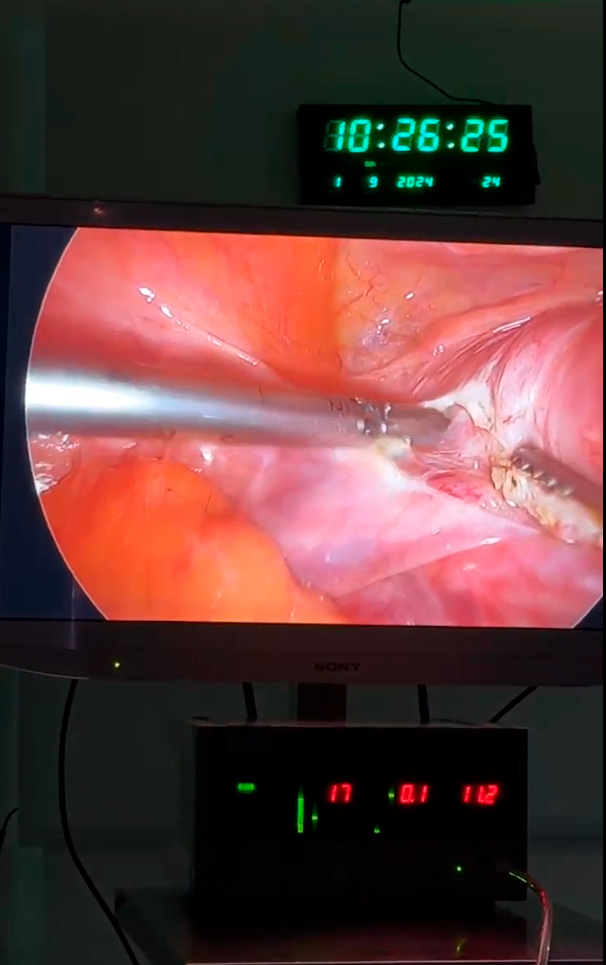

Cirugía ginecológica por laparoscopía

Menor invasión, mejor recuperación.

El Dr. Alberto Velázquez es experto en cirugía ginecológica de mínima invasión, realizando procedimientos por laparoscopía en Tecámac y Zumpango. Esta técnica avanzada permite tratar diversos padecimientos ginecológicos con incisiones pequeñas, menor dolor postoperatorio y una recuperación significativamente más rápida que la cirugía convencional.

Histerectomía laparoscópica

Miomectomía laparoscópica

Cirugía de quistes de ovario

Salpingoclasia laparoscópica